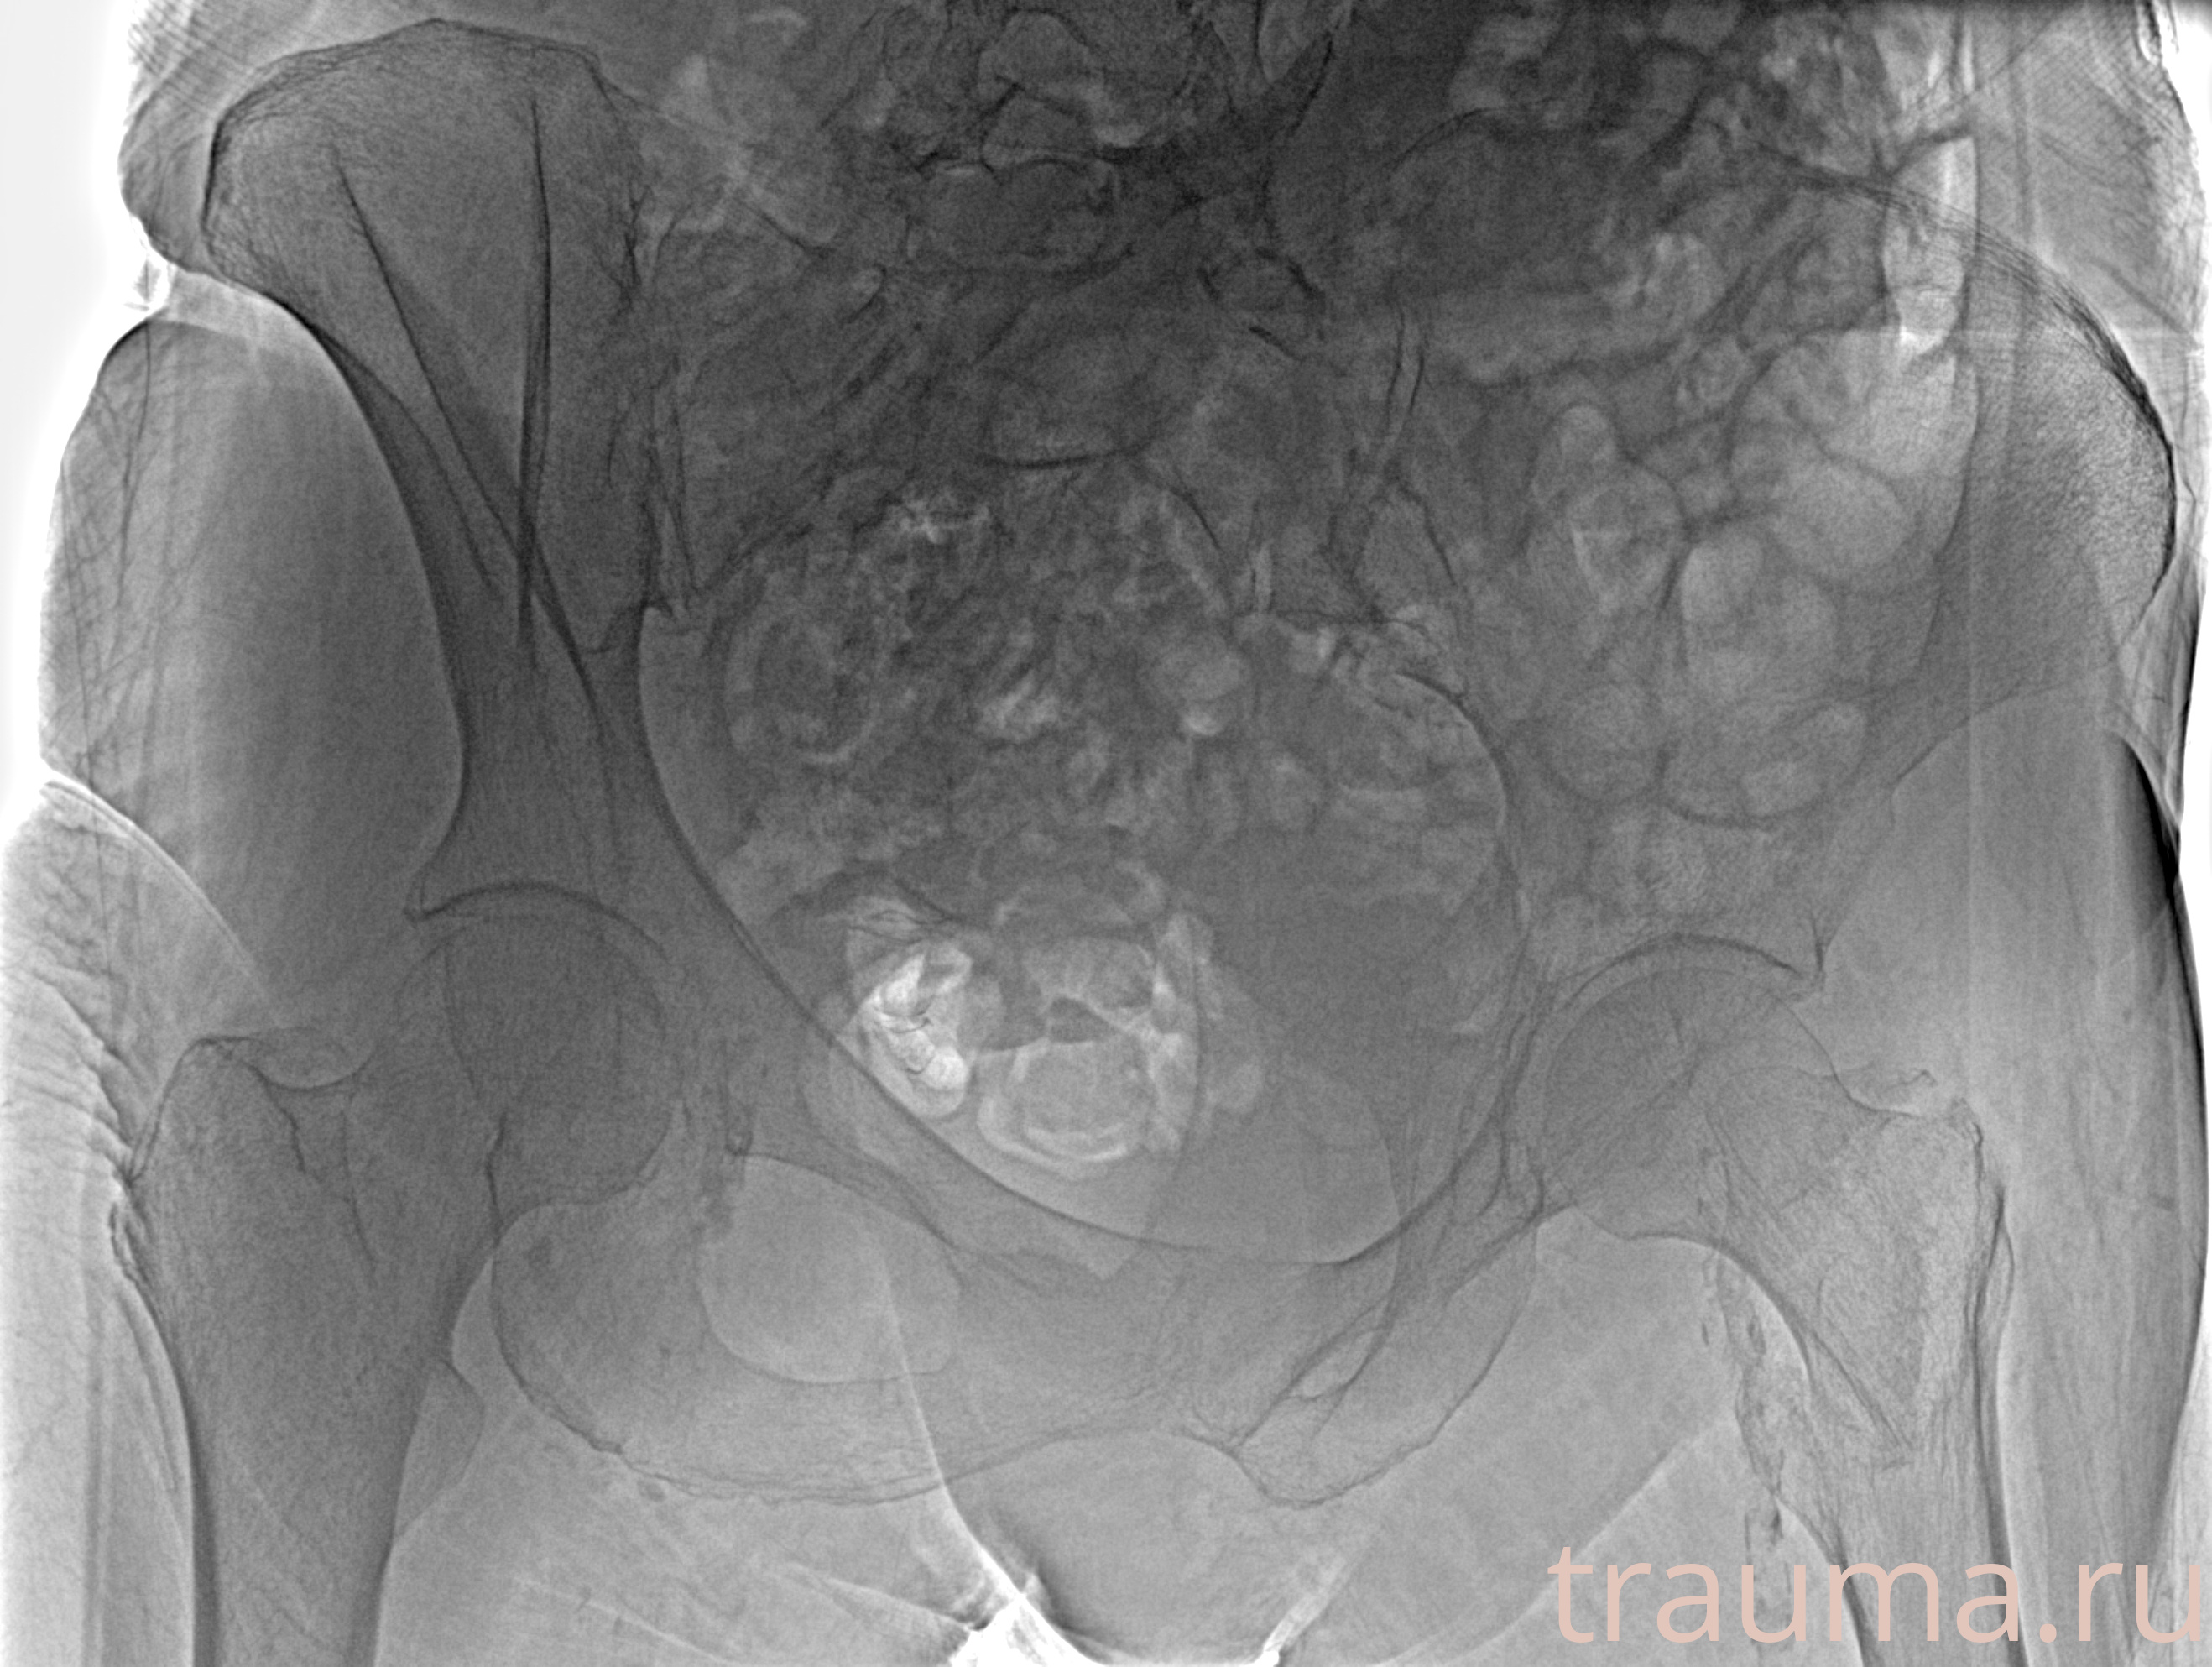

Рентгенограммы

Рентген на дому: по вашему адресу приезжает врач-рентгенолог, травматолог-ортопед с мобильным рентгеновским аппаратом, проводит диагностику травмы или заболевания, делает необходимые рентгенограммы, дает рекомендации по дальнейшему лечению. Получить качественные снимки в домашних условиях возможно благодаря уникальной методике, разработанной МосРентген Центром для института  Склифосовского

при переломе шейки бедра и пневмонии от компании МосРентген Центр - партнера Института имени Склифосовского